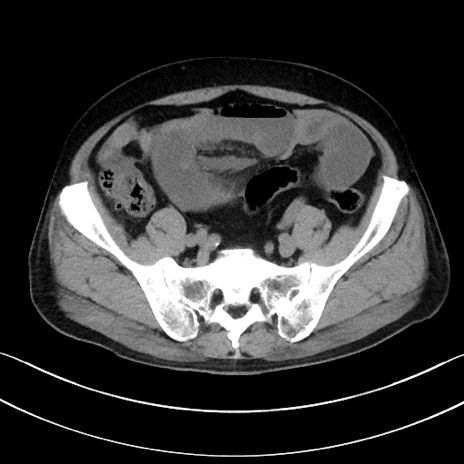

症例15(横断像)

【症例】70歳代男性

【主訴】腹痛

【現病歴】今朝から腹痛あり。全体的に痛い。特に左上の方。排ガスが今日はない。冷や汗が出る。

【既往歴】直腸癌術後

【身体所見】左側腹部〜上腹部に圧痛あり。腹膜刺激症状明らかなではない。軽度反跳痛。左下腹部に術後瘢痕あり。

【データ】WBC 7700、CRP 0.02